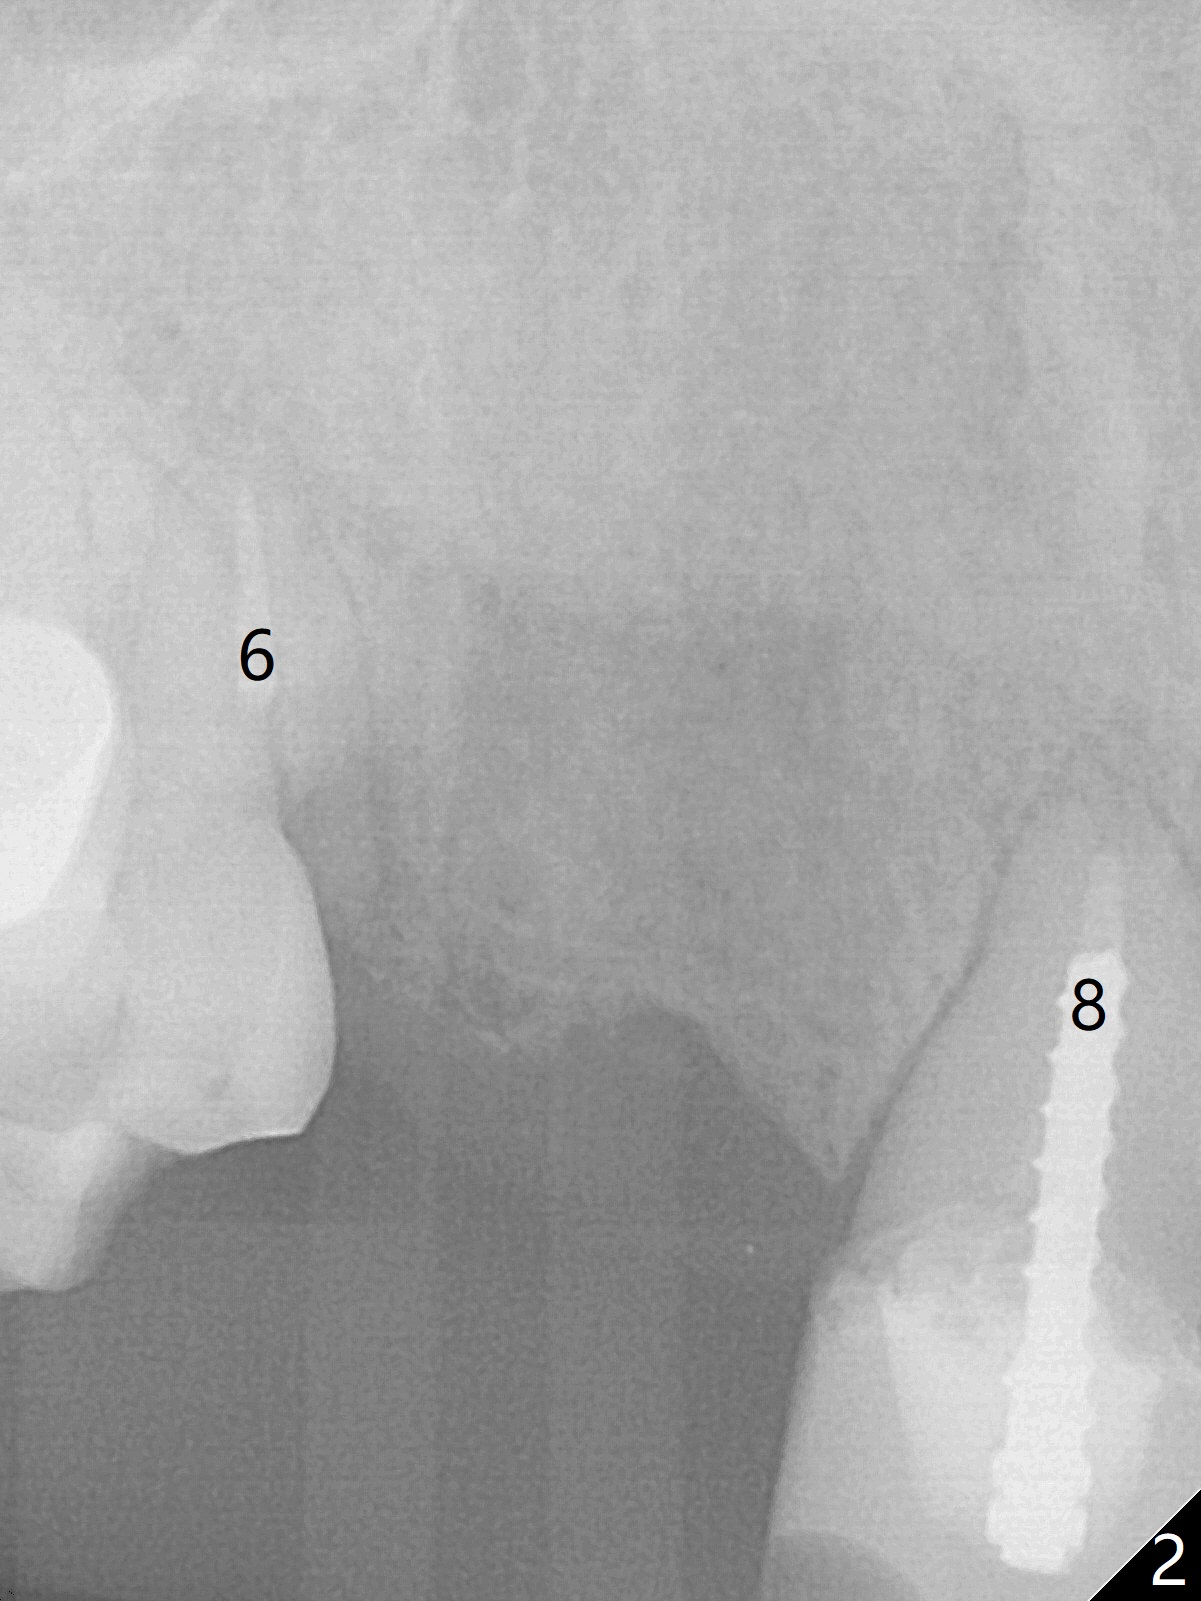

A 38-year-old skinny woman has several missing teeth (Fig.1). Recently a #6-7 cantilever FPD dislodged (Fig.2,3). The buccal plate at #6 must be thin. Socket shield should be indicated, particularly when extraction turns out to be difficult. A 4x13 mm IS implant is going to be inserted as distal as possible to avoid touching the apex of the tooth #5 (Fig.4,5). Since the ridge at #7 is narrow, a 1-piece implant will be placed (possible 2.5x14(2) mm, Fig.5). Take PA after the 1st drills. Take preop photos to show the residual root at #6 and the narrow ridge at #7.